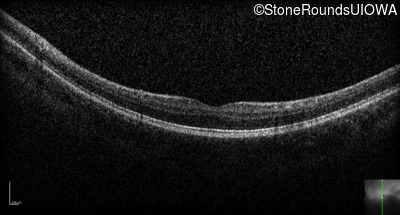

Optical Coherence Tomography - Right - 20/63 -2 sc

Exemplar / OCT Stack

OCT Stack